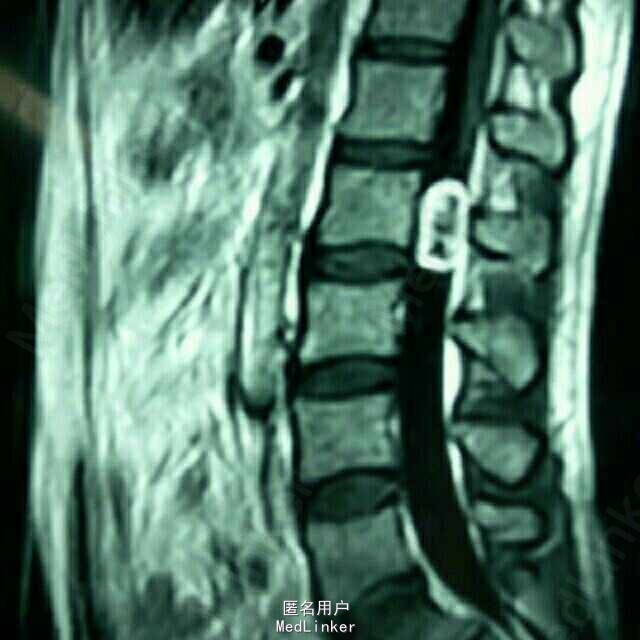

患者四肢肌力及肌张力可,病理反射未引出;鞍区及左侧大腿疼痛,无感觉减退。 腰椎MRI:腰2椎管内占位病变

患者四肢肌力及肌张力可,病理反射未引出;鞍区及左侧大腿疼痛,无感觉减退。 腰椎MRI:腰2椎管内占位

腰2神经鞘瘤 患者在全麻下行腰2椎管内占位病变切除术,术中见病变位于腰2神经马尾,呈囊实性,分界清,包裹神经纤维